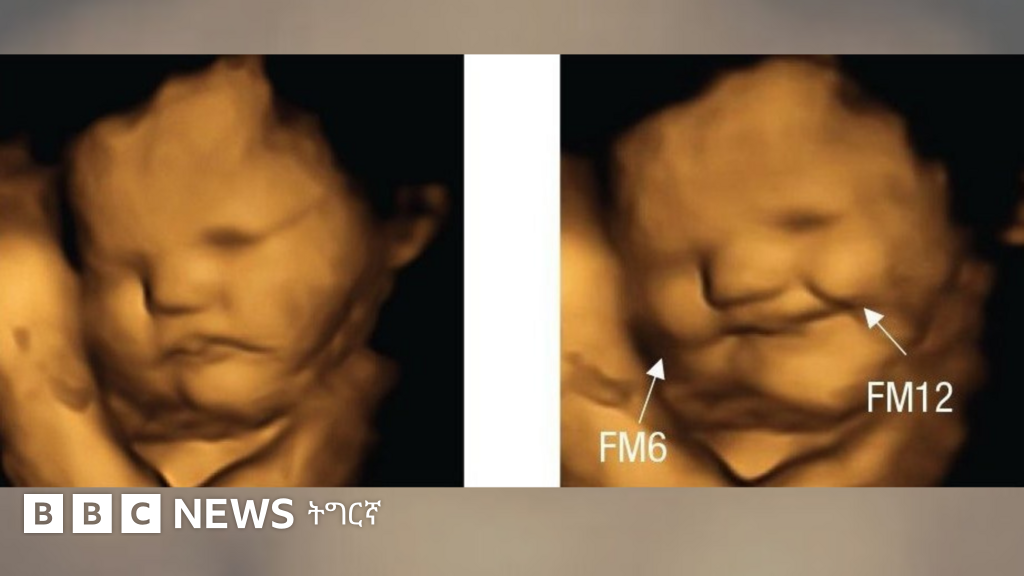

ኣብ ማህጸን ዝርከቡ ዕሸላት፡ ኣደታቶም ካሮት ክበልዓ ከለዋ ‘ፍሽኽ ከምዝብሉ’፡ ሓምሊ ክምገባ ከለዋ ድማ ‘ጽውግ ከምዝብሉ' ኣብ ብሪጣንያ ኣብ 100 ነፍሰጾራትን ዕሸላትን ዝተገብረ ሓድሽ መጽናዕቲ ኣረጋጊጹ።

እቲ ጕጅለ ኣብ መጽሄት ሳይኮሎጂካል ሳይንስ ዘውፅኦ ሓበሬታ ከምዘመልክቶ፡ እተን ኣደታት ነቶም ‘ካፕሱላት’ ካብ ዝውሕጣ ድሕሪ 20 ደቓይቕ፡ ብ4D ኣልትራሳውንድ ክረኣያ እንከለዋ መብዛሕትኦም እቶም ንሓምሊ ዝተቓልዑ ዕሸላት ተጸዊጐም ክብሉ እንከለዉ፣ እቶም ንካሮት ዝተቓልዑ ከኣ ፍሽኽታ ዝመልኦም ነይሮም።

ኣብ ዕሸላት እተን ካብ ክልቲኡ ዘይተወሃበን 30 ነፍሰጾራት ግን ዝዀነ ምላሽ ኣይተራእየን።

ኣብቲ ብኣልትራሳውንድ ዝረአ ጽዋገን ፍሽኽታን "እቲ ንመሪር መኣዛ ምላሽ ዝህብ ዘሎ ምንቅስቓስ ጭዋዳታት ክኸውን ይኽእል'ዩ" ክትብል ተረድእ - ራይስላንድ።